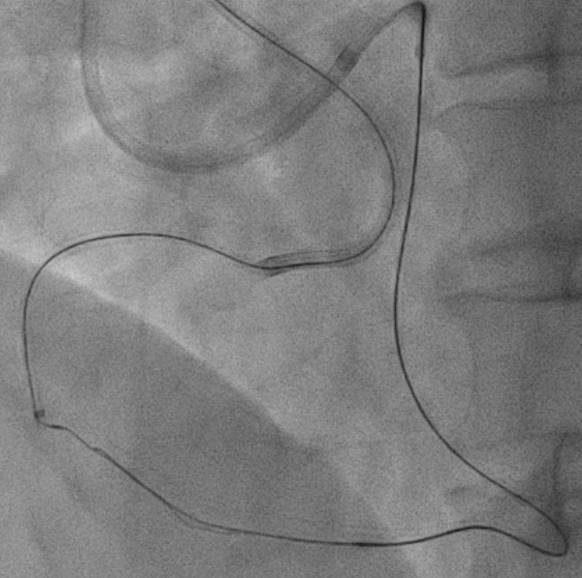

The strategy we plan was antegrade preparation and early retrogradly approach, due to challenging antegrade approach and also distal bifurcation1.XTA+Caravel microcatheter for antegrade preparation, failed advancement in mRCA2.retrograde with suoh03, but could not advance caravel and cosair pro microcatheters through septal channel3.extension catheter use, and balloon dilation for septal channel with low pressure4.caravel could enter dRCA, distal injection5.retrograde wire escalation for calcified CTO: Gaia2, Gaia3, Conquest pro6.kissing wire technique within dRCA7.both side MC could not pass the CTO, despite both side extension catheter use(img: step01)8.intracoronary tip-in, with retrograde wire anchored within AL1(img: step02)9.still failed advancing both side MC10.retrograde balloon dilation, sequentially from distal to middle RCA(img: step03)11.successful antegrade wiring to PL12.lesion preparation and drug-eluting stent placement13.good final angiography results